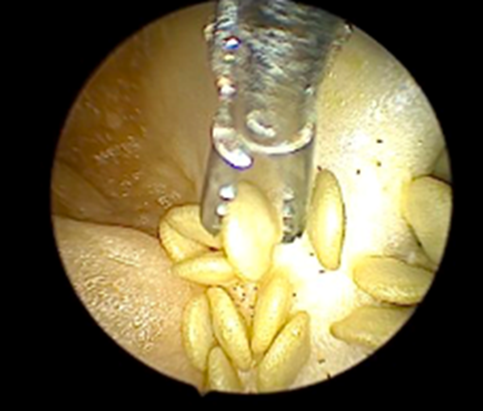

Instruments and Technique: Each training set up had a 2.9mm 30° hysteroscope with a 5mm operative sheath, connected to a camera control unit and monitor, with an LED light source as the primary operating instrument. Hysteroscopic scissors and graspers were the instruments available for use. Bipolar loop resectoscopes connected to underwater diathermy electrosurgical generators were also provided. Distension media used was 0.9% normal saline irrigated with a Hysteromat Ò (Karl Storz SE & Co KG Tuttlingen Germany) providing the facility to control inflow, outflow and fluid deficit estimation like real surgery. The trainees were guided on correct assembly and handling of the hysteroscope and then underwent hands on training on the standard bell pepper model with a set of prescribed exercises under the guidance of proctors. The participants were asked to perform diagnostic hysteroscopy first to build hand-eye coordination and understand the movement of the hysteroscope. The trainees next used scissors and graspers on the capsicum seeds to simulate polypectomy, scissors to simulate septum resection and metroplasty and used the natural crevices of the pepper to practice tubal cannulation (Figure 1 – 6).

Figure 2: Polypectomy with grasper

Figure 3: Polypectomy with scissor